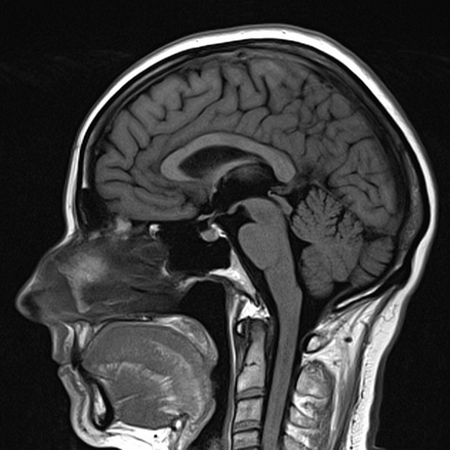

МРТ головного мозга: анатомические снимки и объяснения